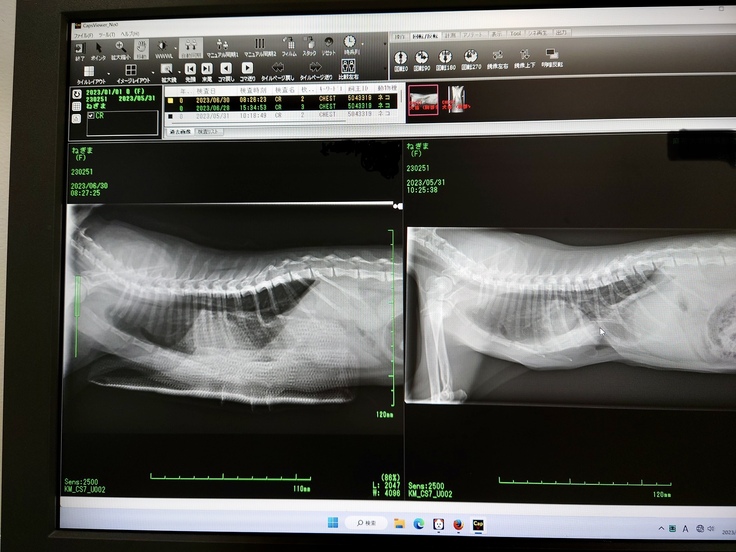

最近保護した子猫の呼吸に異変があり、病院に行った所、漏斗胸と診断されました。

骨が出来あがる6ヶ月位までに手術する必要があると言われた為、6月下旬に手術をしました。

最近保護した子猫の呼吸に異変があり、保護猫も診察している病院に行った所、漏斗胸と診断されました。そちらの病院では手術は出来ず大学動物病院を紹介されました。

骨が出来あがる6ヶ月位までに手術する必要があると言われました。

担当獣医師による術式説明の図です